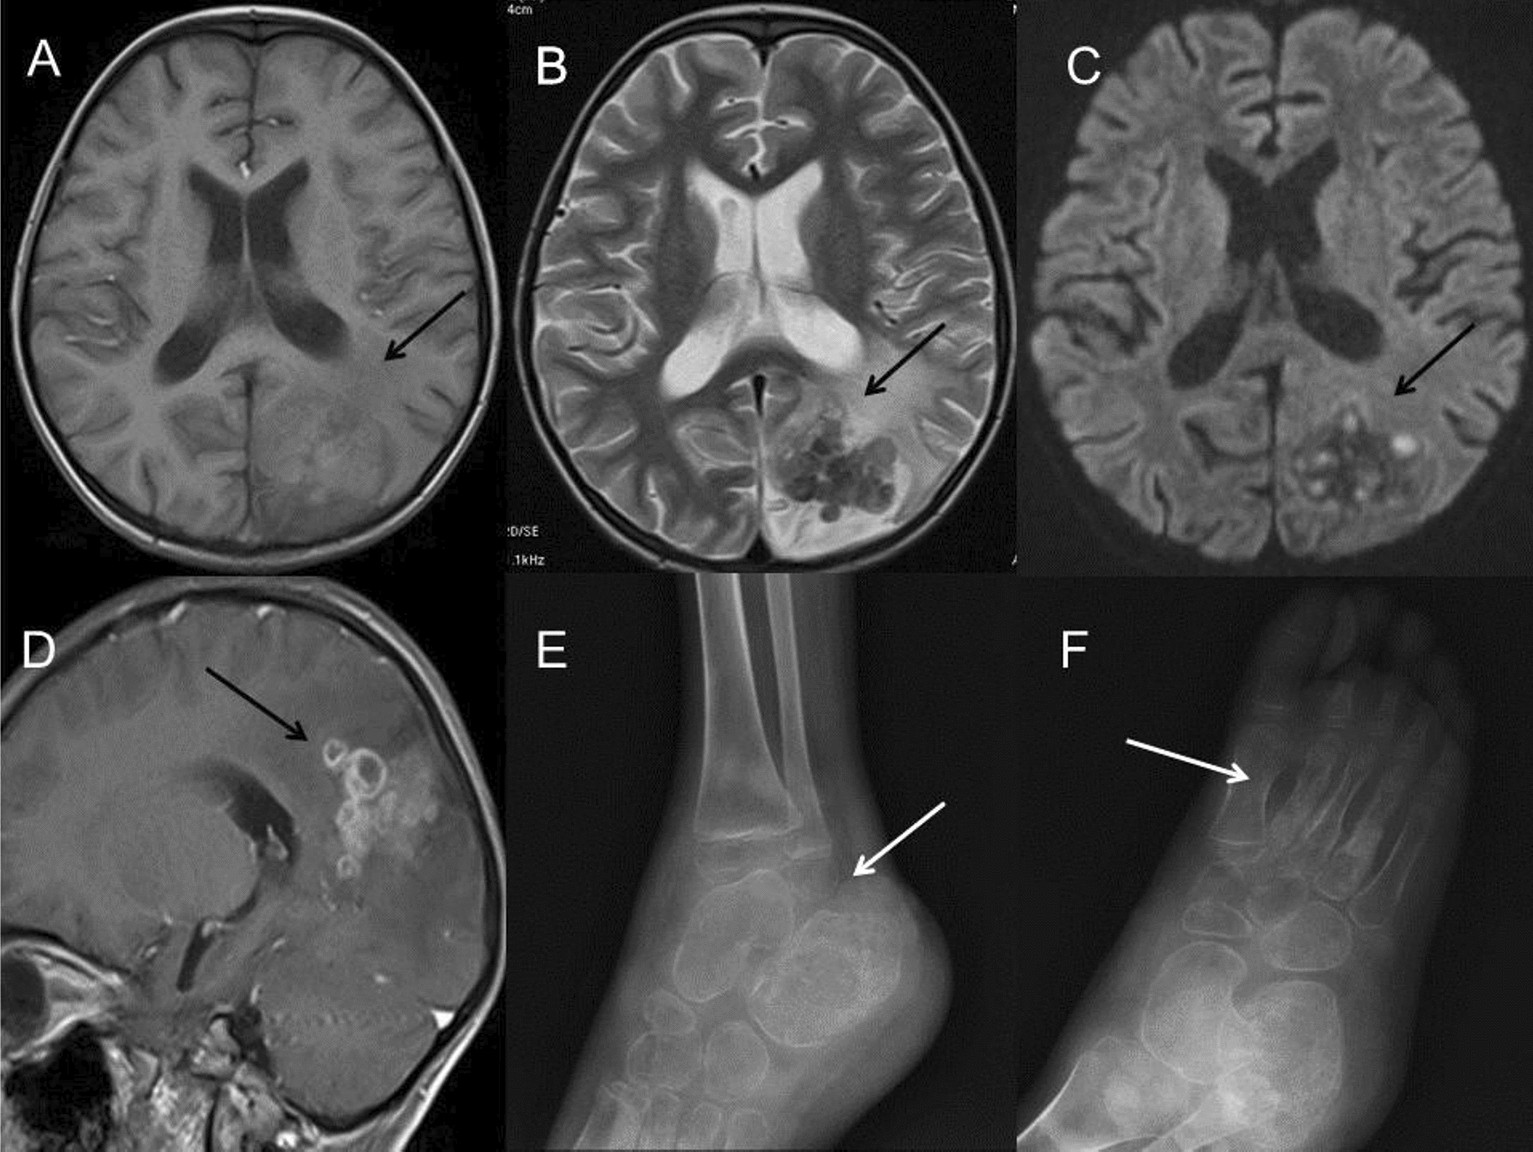

Figure 6

A 5-year-old boy with infection of TB. (A–D) MRI showed multiple small cerebral abscesses (long arrow) in the left parietal and occipital lobes, which had high intensity on T1WI (A), low intensity on T2WI (B), high intensity on DWI sequence (C) and annular enhancement on post-contrast T1WI (D), suggesting the presence of caseous necrosis. Extensive cerebral edema could be found around the lesions. (E,F) Osteomyelitis in the right tibia and foot was found in the same patient, demonstrating local bone erosions and osteosclerosis in the lower metaphysis of the tibia, the calcaneal and the 2nd–4th metatarsal bones (long arrow). Periosteal thickening along the metatarsal bones and swelling soft tissue of the right ankle and foot were found.